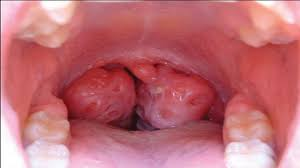

Mafindofindo ni mashambulizi ya virusi au bakteria kwenye tezi za koo zijulikanazo kama findo. Asilimia 15 mpaka 30 ya mashambulizi haya yanatokana na bakteria ila asilimia kubwa hutokana na virusi.

• Utando katika findo

• Utando mweupe koni